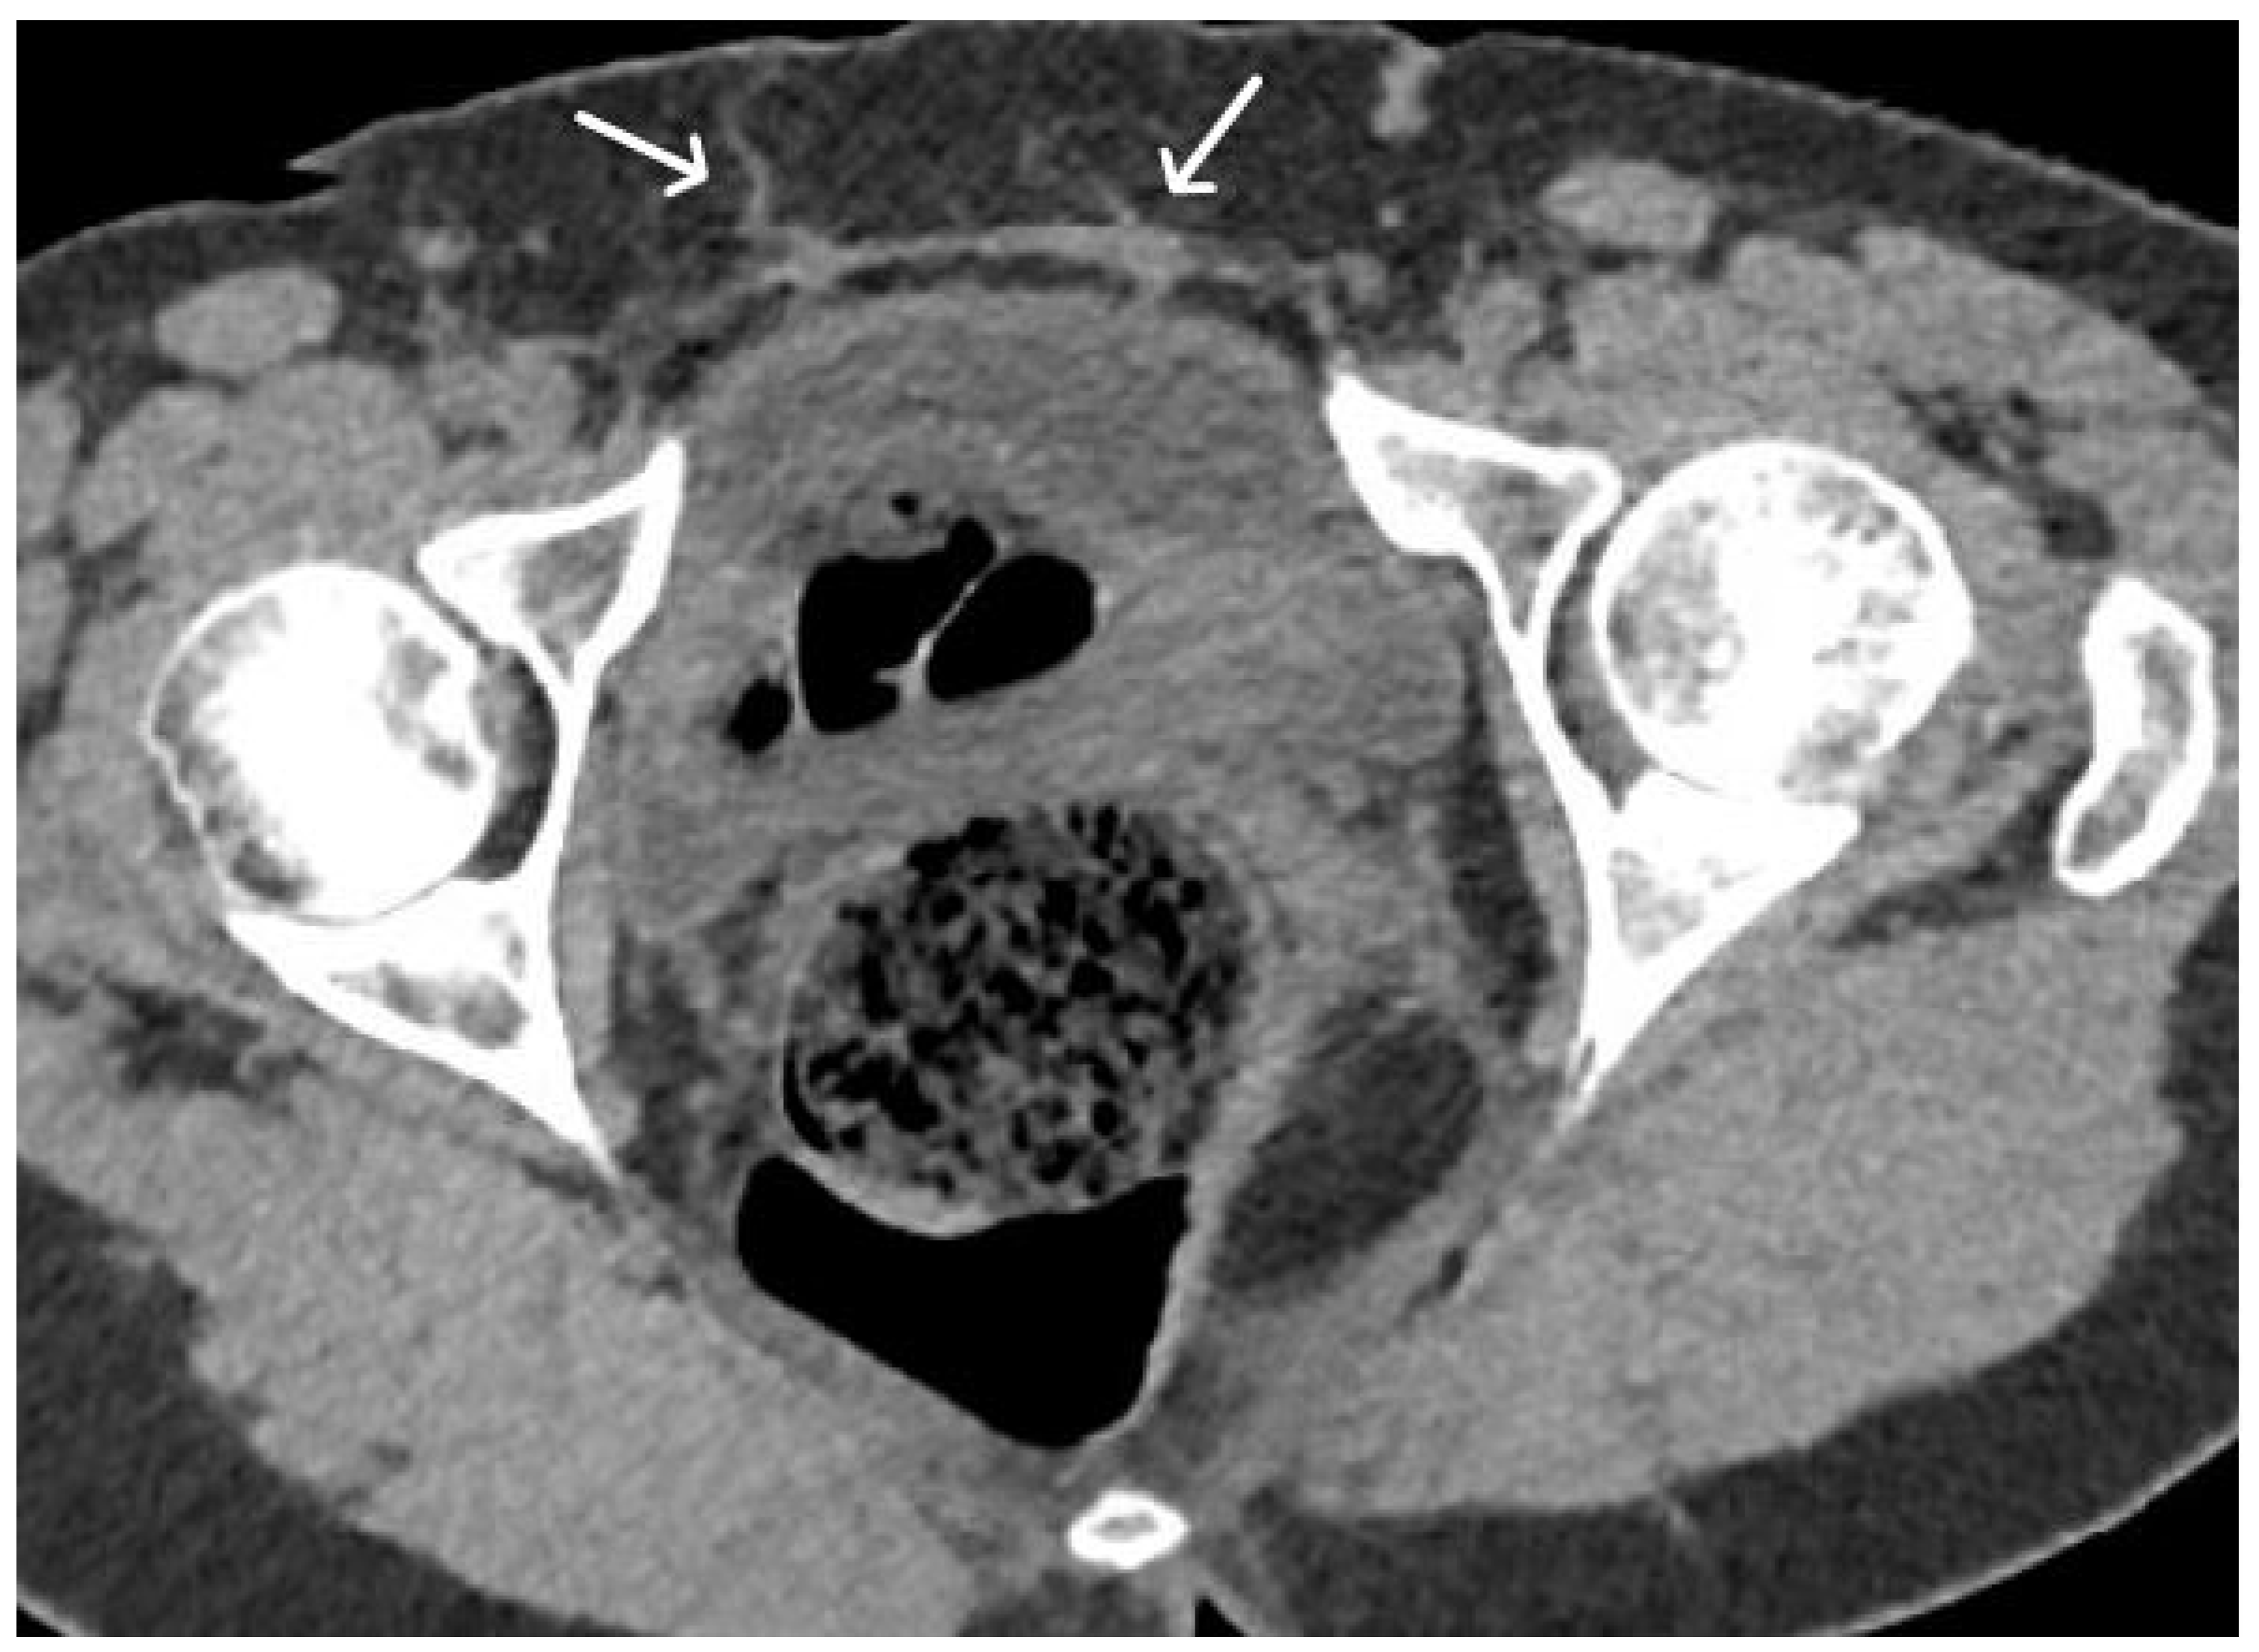

4. Urethral Mesh in Oncological Patients